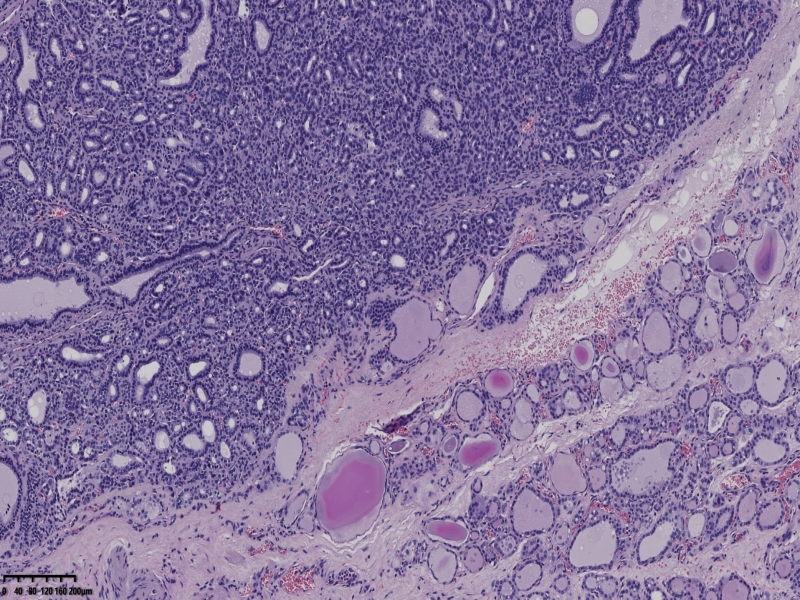

男、69、甲状腺左叶肿物,部分为囊性,囊内可见乳头状结构,上皮核重叠,没有核沟,没有毛玻璃样改变,没有核内假包涵体。255427

部分区域瘤组织与周围甲状腺组织分界明显,没有包膜样结构,滤泡结构为主,细胞异型明显。